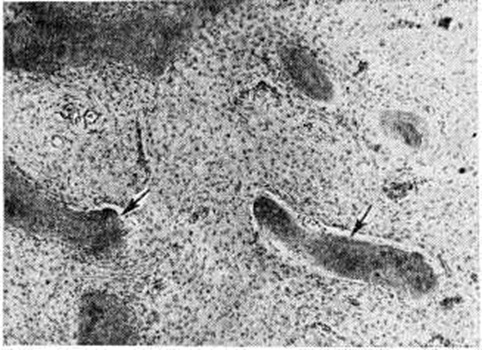

При микроскопическом исследовании поражённых отделов костей обнаруживается волокнистая соединительная ткань, представленная коллагеновыми, ретикулиновыми волокнами и фибробластоподобными клетками, среди которых располагаются примитивные костные балки, распределяющиеся бессистемно (рисунок 1). Нередко периферические отделы костных балок состоят из остеоидной ткани, реже балки целиком состоят из этой ткани. Иногда формирующиеся костные структуры крайне примитивны и имеют вид более или менее обособленных сгущений коллагеновых волокон без отложения в них солей кальция. Эти структуры рассматривают как предстадию образования костных балок. У разных больных и в различных очагах Фиброзная остеодисплазия одного и того же больного и даже в разных участках одного очага гистологический картина может быть неодинаковой. Она различается по характеру костных структур, количественному соотношению этих структур с волокнистой тканью, морфологии клеток и плотности расположения волокон. У некоторых больных в патологический очагах или их участках развивается более или менее густая сеть костных балок, иногда напоминающая губчатую остеому (смотри полный свод знаний). Среди волокон соединительной ткани встречаются скопления остеокластов; изредка обнаруживаются участки типа остеобластокластомы (смотри полный свод знаний), иногда выявляются скопления ксантомных клеток (смотри полный свод знаний: Ксантома).

Рис. 1.

Микропрепарат участка ткани из патологического очага при фиброзной остеодисплазии: волокнистая соединительная ткань с единичными бессистемно расположенными примитивными костными балками (указаны стрелками); окраска гематоксилин-эозином, ×105.